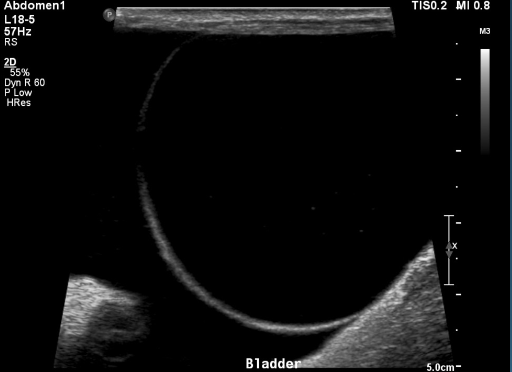

19

What is shown in these images?

A

anechoic effusion around liver (left) and bladder (right)

20